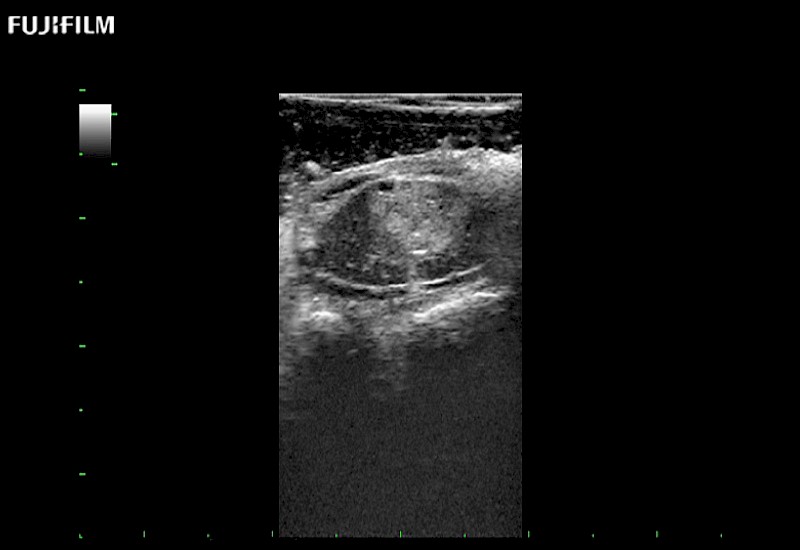

Exclusive 10mm side‐fire linear array transducer with 2.87mm diameter is ideal for real‐time visualization through and behind structures and instant, scalable definition of anatomy and vascularity including the ability to delineate and define tumor margins.

Main Specifications: